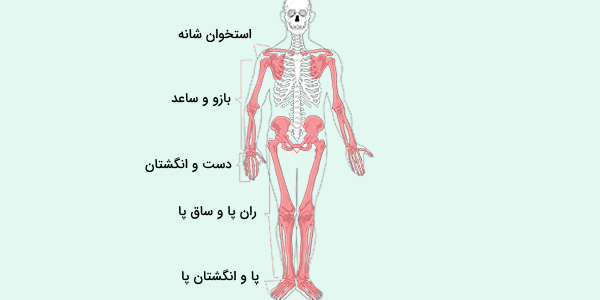

عکس اسکلت بدن انسان. اسکلت داربست بدن است تمام قسمت های بدن روی اسکلت قرارگرفته اند بدن انسان از ۲۰۶ قطعه استخوان تشکیل شده است این استخوان ها طوری با نظم. هر قسمت بدن از انواع مختلف سلول تشکیل شده است. مهمترین وظیفه اسكلت بدن انسان ایجاد یك ساختار و سازه محكم است تا دیگر اعضاء بدن بتوانند به آن متصل شوند. سازه و چهارچوب اصلی بدن.

اسکلت داربست بدن است تمام قسمت های بدن روی اسکلت قرارگرفته اند بدن انسان از ۲۰۶ قطعه استخوان تشکیل شده است این استخوان ها طوری با نظم کنار هم قرار گرفته اند که انسان را قادر می سازد حرکات دقیقی داشته باشد. بدون اسكلت بدن مانند كرم شل و نرم است و این نوع شكل بندی نمیتواند. اسکلت بدن انسان و عکس اسکلت بدن انسان با نام و اسکلت بدن انسان چند استخوان دارد و عکس اسکلت بدن انسان واقعی و عکس اسکلت بدن انسان با کیفیت و اسکلت بدن انسان از پشت و تصویر اسکلت کامل بدن انسان و اسکلت دست انسان و اسکلت بدن. معرفی بدن انسان اسکلیت.

اسکلت داربست بدن است تمام قسمت های بدن روی اسکلت قرارگرفته اند بدن انسان از 206 قطعه استخوان تشکیل شده است این استخوان ها طوری با نظم کنار هم قرار گرفته اند که انسان را قادر می سازد حرکات دقیقی داشته باشد. اسكلت به بدن شكل میدهد. عکس اسکلت بدن انسان زن و مرد آناتومی ساتین 16 سپتامبر 2017.